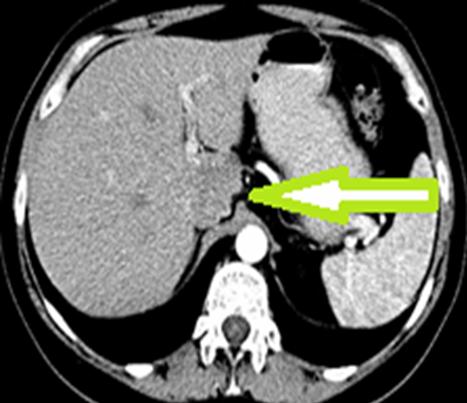

Pacienta a fost o femeie de 50 de ani. Aceasta a fost diagnosticată cu o tumoare masivă hepatică, preponderent S I, cu invazia venei cave inferioare porțiune retrohepatică și prezența simptomelor pozitive caracteristice sindromului de ocluzie a venei cave inferioare. La internare, femeia acuza dureri moderate în regiunea lombară, edeme și pastozitate a membrelor inferioare. Diagnosticul preoperator a fost stabilit pe baza investigatii CT cu contrastare in regim angiografic. Până acum așa amplasare a tumorii a fost considerată inoperabilă. Potrivit prof. univer., dr. Adrian Hotineanu, până acum acești pacienți erau refuzați pentru tratament radical și primeau doar îngrijiri paliative fără efect, care duceau inevitabil la deces. Medicul a menţionat că “toate acestea pot fi depășite doar prin tratament radical, prin rezecția hepatică cu tumoare și rezecția venei magistrale. Numai această metodă este potențial curativă și poate oferi vindecare”.

Astfel, pentru a salva viaţa pacientei, doctorii au rezecat o parte de ficat, purtător de tumoare, au mobilizat şi lanțuit porțiunea retrohepatică a venei cave inferioare. Ulterior s-a rezecat în bloc cu tumoare, care s-a înlocuit cu proteză vasculară. Medicii spun că perioada postoperatorie decurge favorabil. La moment pacienta se simte bine şi se pregatește pentru externare.